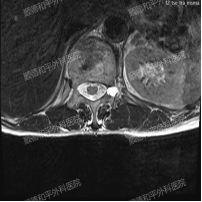

经过询问病史、详细查体及完善腰椎检查后,发现吴阿姨是因为腰椎间盘突出伴神经根的机械性卡压导致左下肢的放射性疼痛。

最终诊断为:“腰椎退行性变、腰椎左凸侧弯畸形、T12椎体压缩性改变、L5/S1椎间盘膨出伴真空变性、多节段椎管狭窄”等复杂腰椎病变,建议手术治疗。

再加上患者高龄且合并高血压等基础疾病,传统开放手术风险较高,保险决定采用微创手术的方式,并耐心的向吴阿姨解释了手术的必要性,及微创手术治疗的优势,且手术由经验丰富的张哉炯主任主刀,增强吴阿姨配合治疗的信心。

手术过程中,决定采用后入L5/S1椎间盘摘除、L4/5椎间盘植骨融合内固定术治疗。在麻醉科、手术室通力配合下,不到一个小时手术顺利完成。